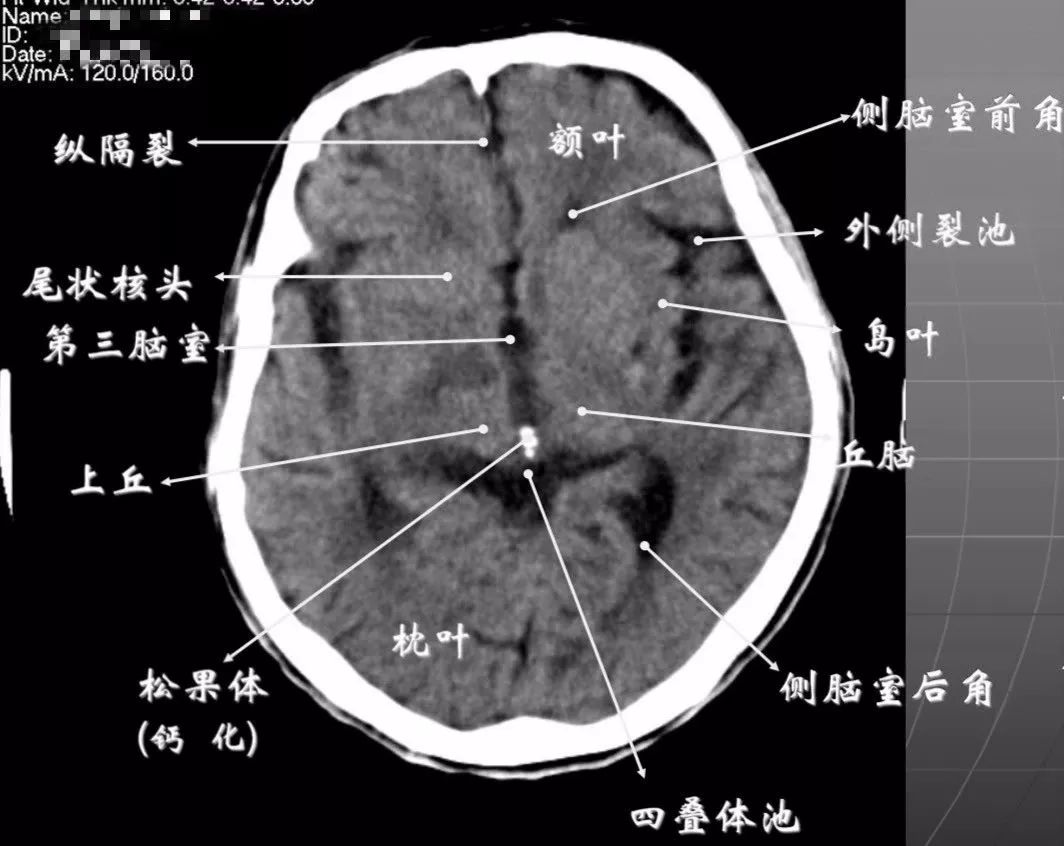

4、第三脑室上部层面基底核、丘脑。

内囊前脚(前肢);尾状核和豆状核之间。

内囊膝部和后脚(后肢):位于豆状核(由外侧的壳核和内侧的苍白球组成)及丘脑之间。

壳核的外侧:外囊、屏状核、最外囊、岛叶(脑岛)。

四叠体池:两侧枕叶之间,池内有松果体,向前与第三脑室连接。

基底节(基底核):埋藏在两侧大脑半球深部的灰质核团,是组成锥体外系的主要结构。

基底节区:概念不清。可能包括:基底节、黑质、红核、及其周围白质区域。

内囊:位于丘脑、尾状核、豆状核之间的白质区,是由上、下行的传导束密集而成。分为三部分:前肢、膝部、后肢。膝部有皮质脑干束;后肢有皮质脊髓束、丘脑皮质束、听辐射和视辐射。

外囊:是位于屏状核和豆状核之间的白质带,主要由岛叶发出的皮质被盖纤维组成。